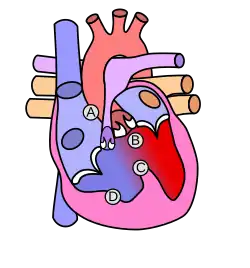

![]() | |

| Diagram of a healthy heart and one with tetralogy of Fallot | |

Tetralogy of Fallot (TOF), formerly known as Steno-Fallot tetralogy,[9] is a congenital heart defect characterized by four specific cardiac defects.[4] Classically, the four defects are:[4]

- Pulmonary stenosis, which is narrowing of the exit from the right ventricle;

- A ventricular septal defect, which is a hole allowing blood to flow between the two ventricles;

- Right ventricular hypertrophy, which is thickening of the right ventricular muscle; and

- an overriding aorta, which is where the aorta expands to allow blood from both ventricles to enter.

Four malformations

"Tetralogy" denotes four parts, here implying the syndrome's four anatomic defects.[2] This is not to be confused with the similarly named teratology, a field of medicine concerned with abnormal development and congenital malformations (including tetralogy of Fallot). Below are the four heart malformations that present together in tetralogy of Fallot:

| Pulmonary Infundibular Stenosis | A narrowing of the right ventricular outflow tract. It can occur at the pulmonary valve (valvular stenosis) or just below the pulmonary valve (infundibular stenosis).[4] Infundibular pulmonic stenosis is mostly caused by the overgrowth of the heart muscle wall (hypertrophy of the septoparietal trabeculae),[42] however, the events leading to the formation of the overriding aorta are also believed to be a cause. The pulmonic stenosis is the major cause of the malformations, with the other associated malformations acting as compensatory mechanisms to the pulmonic stenosis.[43] The degree of stenosis varies between individuals with TOF and is the primary determinant of symptoms and severity. This malformation is infrequently described as sub-pulmonary stenosis or subpulmonary obstruction.[44] |

| Overriding aorta | An aortic valve with biventricular connection, that is, it is situated above the ventricular septal defect and connected to both the right and the left ventricle. The degree to which the aorta is attached to the right ventricle is referred to as its degree of "override." The aortic root can be displaced toward the front (anteriorly) or directly above the septal defect, but it is always abnormally located to the right of the root of the pulmonary artery. The degree of override is extremely variable, with 5–95% of the valve being connected to the right ventricle.[42] |

| Ventricular septal defect (VSD) | A hole between the two bottom chambers (ventricles) of the heart. The defect is centered around the most superior aspect of the ventricular septum (the outlet septum), and in the majority of cases is single and large. In some cases, thickening of the septum (septal hypertrophy) can narrow the margins of the defect.[42] |

| Right ventricular hypertrophy | The right ventricle is more muscular than normal, causing a characteristic boot-shaped (coeur-en-sabot) appearance as seen by chest X-ray. Due to the misarrangement of the external ventricular septum, the right ventricular wall increases in size to deal with the increased obstruction to the right outflow tract. This feature is now generally agreed to be a secondary anomaly, as the level of hypertrophy tends to increase with age.[45] |